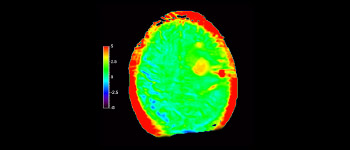

Glioblastoma

Brain with glioblastoma

with 3D APT

3D APT (Amide Proton Transfer) is a unique, contrast-free, brain MR imaging method addressing the need for more confident diagnosis in neuro oncology. 3D APT uses the presence of endogenous cellular proteins, to produce an MR signal that directly correlates with cell proliferation, a marker of tumoral activity. 3D APT can support trained medical professionals in differentiating low grade from high grade gliomas and, in differentiating tumor progression from treatment effect1.